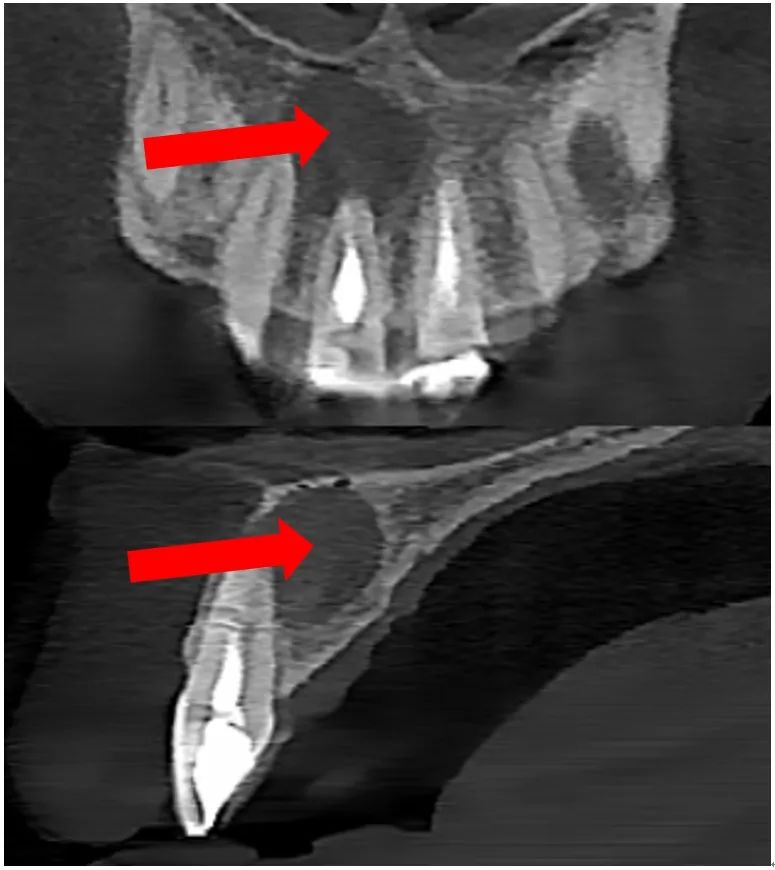

治疗前CBCT

经过口内检查和口腔颌面锥形束CT(CBCT)检查,医生发现陈先生的牙齿之前已经做过根管治疗,但围绕根管治疗后的牙齿根尖形成了一个囊肿,由于囊肿较大,旁边的牙齿也受到了影响。陈先生的牙根周围出现了“根尖囊肿”,“根尖囊肿”是什么,是什么原因引起的,对我们的牙齿有什么影响呢?

根尖囊肿是牙源性的颌骨囊肿,是一种慢性病变,多由于牙髓炎未经治疗或者治疗不彻底,迁延不愈后发展成慢性根尖周炎而形成根尖囊肿。由于牙齿根尖部的慢性炎症、肉芽组织的长期反复刺激,导致牙周膜内的上皮残余不断增生,增生的上皮团块中央发生变性与液化,周围组织不断渗出液体,逐渐形成囊肿,因其围绕在患牙牙根尖周围,故亦称为“根尖囊肿”。它生长较慢,一般无自觉症状,初期可观察到由于牙髓坏死引起的牙齿颜色变化,或可表现为反复出现、或伴有流脓的牙龈瘘管,较多患者往往等囊肿生长到较大才发现,此时根尖部的牙龈黏膜呈半球形隆起,手压时像有乒乓球感,有弹性,压迫邻近牙时,可引起邻牙松动或移位。